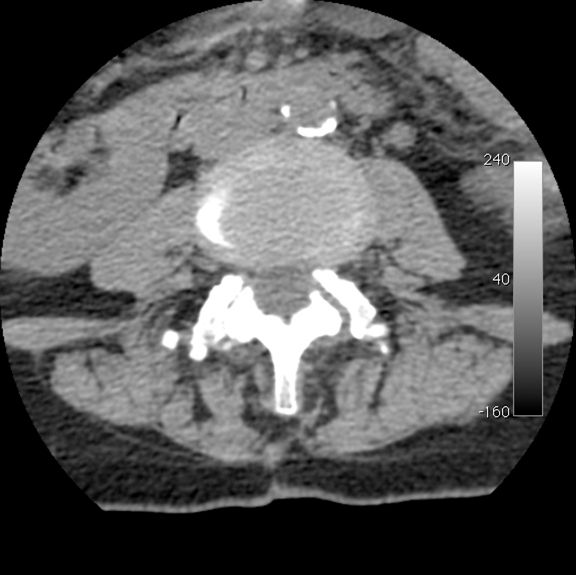

The diagnosis of LSS was then confirmed with imaging studies, either CT or MRI (Fig. 1). Dynamic myelography was useful to search for any compression not detected on the static images.